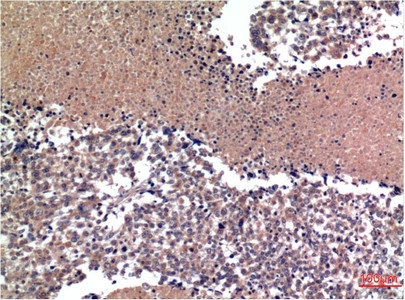

Immunohistochemical analysis of paraffin-embedded Human Tonsil Tissue using Cyclin B1 Mouse mAb diluted at 1:200.